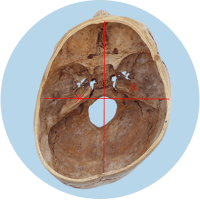

Das größte Problem besteht darin, dass der Kopf in seiner Struktur verändert wird – die Schädelbasis wird schief. Davon sind hauptsächlich die Stellung der Ohren (Gleichgewichtsorgane), die Kiefergelenke (Zahnfehlstellungen) und Halswirbelkörper betroffen. Kritisch wird dies spätestens, wenn sich die Kinder zum Ende des 1. Lebensjahres aufrichten und eine schiefe Wirbelsäulenhaltung entwickeln.

Die verschobene Position der Gleichgewichtsorgane ist durch die roten Kreuze gekennzeichnet.